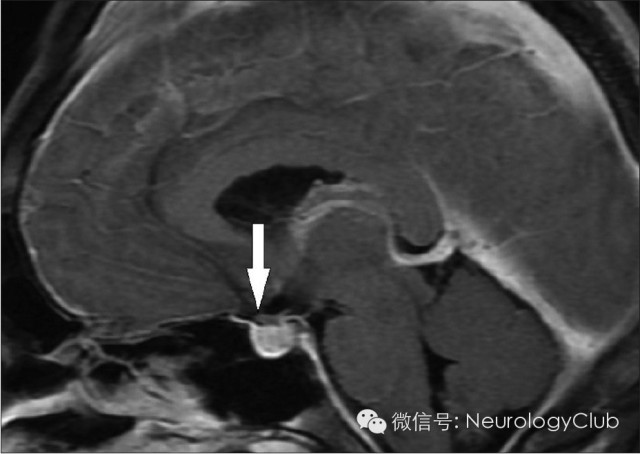

根据Monro-Kellie假说,颅内腔容积恒定不能扩张,颅内容物的总量之和即脑组织、脑血流量及脑脊液量的总和应保持恒定不变。如果其中一种成份增加必然导致另外两种成份的减少;反之,当颅内低压综合征患者的脑脊液容量减少时,必然导致另外两种成份增加。由于脑组织容积相对恒定,所以只能依靠脑血流量的变化起到代偿作用。因为软脑膜及脑实质血管有血脑屏障而硬脑膜没有,所以这种静脉的充血扩张只能表现在硬脑膜和脑静脉窦上。影像学则相应地表现为硬脑膜、硬脊膜弥漫性增厚、增强以及颅内静脉窦的扩张,垂体硬膜充血则表现为垂体增大。如果脑静脉充血扩张仍不能完全代偿,还可进一步表现为硬膜下积液。另外,在正常情况下,脑组织是漂浮在脑脊液中的,在脑脊液容量减少时,脑脊液对脑组织的浮力作用下降使脑组织向下移位,称为下垂脑,构成了影像学上的另外一组表现。

(5)脑组织下沉(Sagging of the brain)